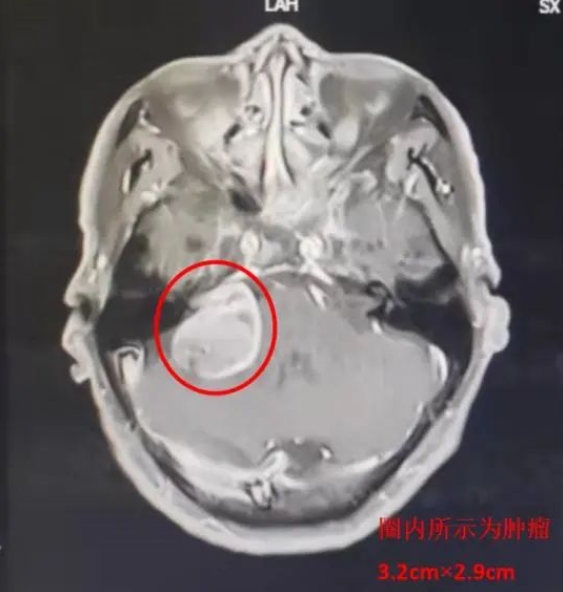

患者马某,69岁,因耳鸣及头晕2年,严重影响日常生活,3月19日就诊于MILAN.COM神经外科一病区。入院诊断:右侧听神经瘤。

3月28日,由主任医师赵金安监台,主治医师段吉强主刀,历时8小时顺利完成手术,术中肿瘤全切、各神经血管完整解剖保留,术中出血约200ml。术后1小时患者即苏醒,生命体征平稳。